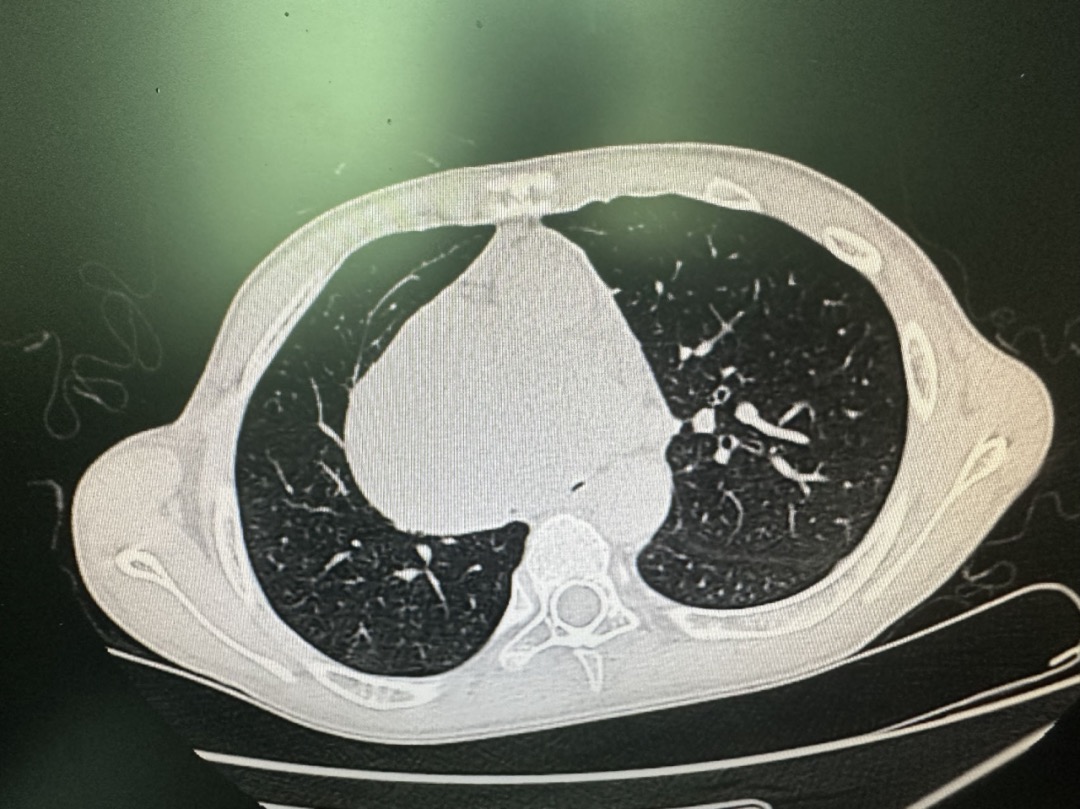

这名13岁患儿,陈主任非常清楚,是一名巨大纵隔肿瘤患者,病情进展迅速,肿瘤基本占据了整个中纵膈,压迫了气管,隆突及双侧支气管,其中右支气管完全被压瘪,仅剩左支气管残余不到10%口径的管腔勉强维持氧合。现在患者已端坐位呼吸,三凹征,随时有窒息风险。9日下午针对此患者已行全院多学科会诊,为保障患者安全,专家建议备好ECMO(体外膜肺氧合)。